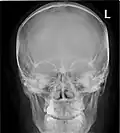

Lateral projection of the paranasal sinuses

Paranasal sinuses are a group of four paired air-filled spaces that surround the nasal cavity.[1] The maxillary sinuses are located under the eyes; the frontal sinuses are above the eyes; the ethmoidal sinuses are between the eyes, and the sphenoidal sinuses are behind the eyes. The sinuses are named for the facial bones and sphenoid bone in which they are located. The role of the sinuses is still debated.